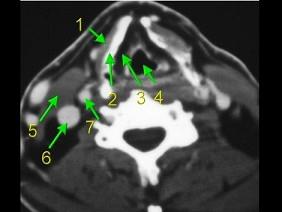

问题 下面是一颈部CT图,其中结构标志不正确的是 ( )

选项 A、6为颈内动脉 B、7为颈内动脉 C、3为声门旁隙 D、5为胸锁乳突肌 E、2为甲状软骨

答案 A